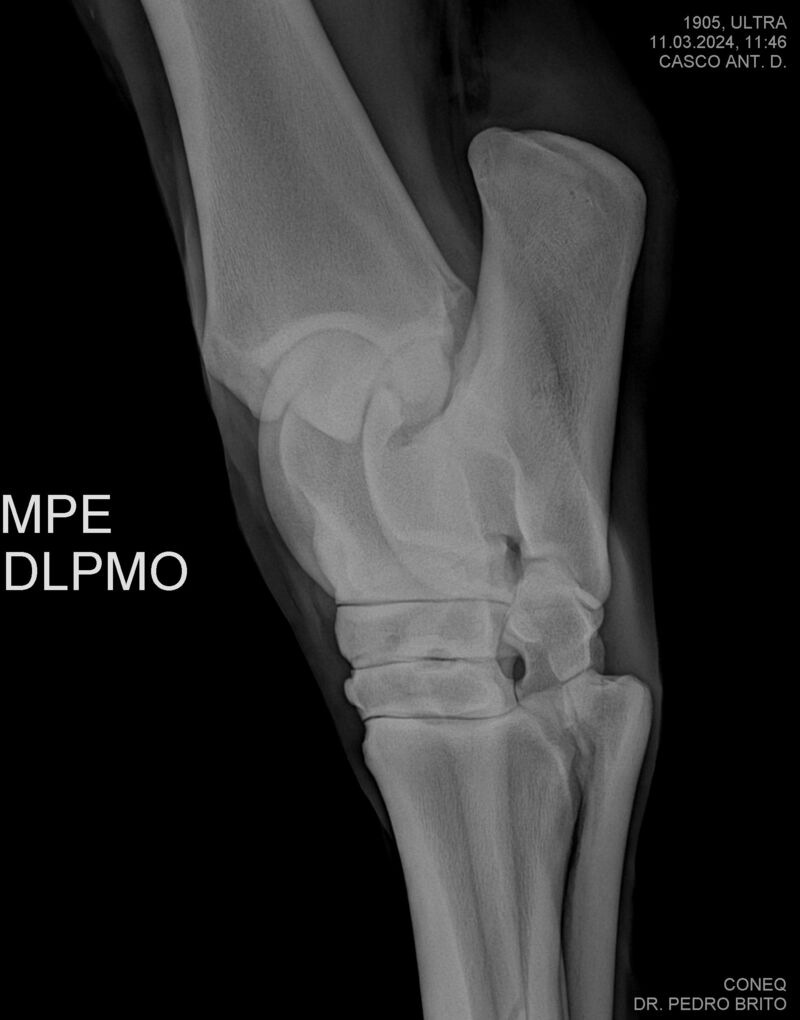

ULTRA DO CACH

Raça: BRASILEIRO DE HIPISMO

Sexo: CASTRADO - CASTRADO

Nascimento: 22/11/2020

Altura Aproximada: 1,67

Pel.: CASTANHO

Registro: 25966-BH

Vend.: HARAS CACHOEIRINHA

Local : PIRASSUNUNGA/SP